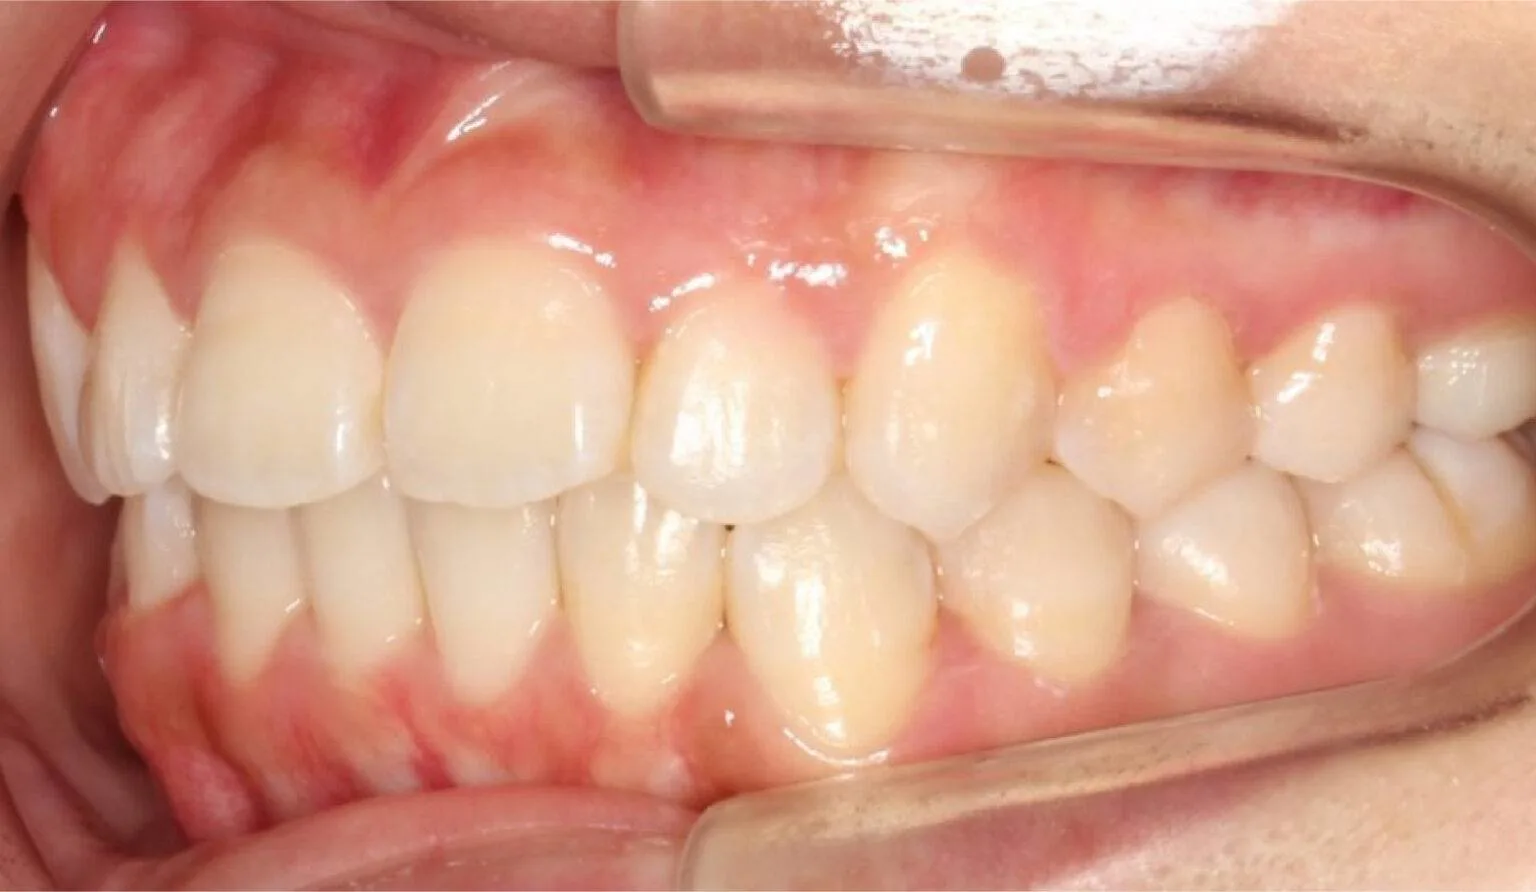

Before overbite treatment showing upper teeth protrusion at SmileBox Dental Clinic After overbite treatment showing corrected bite and balanced smile at SmileBox Clinic